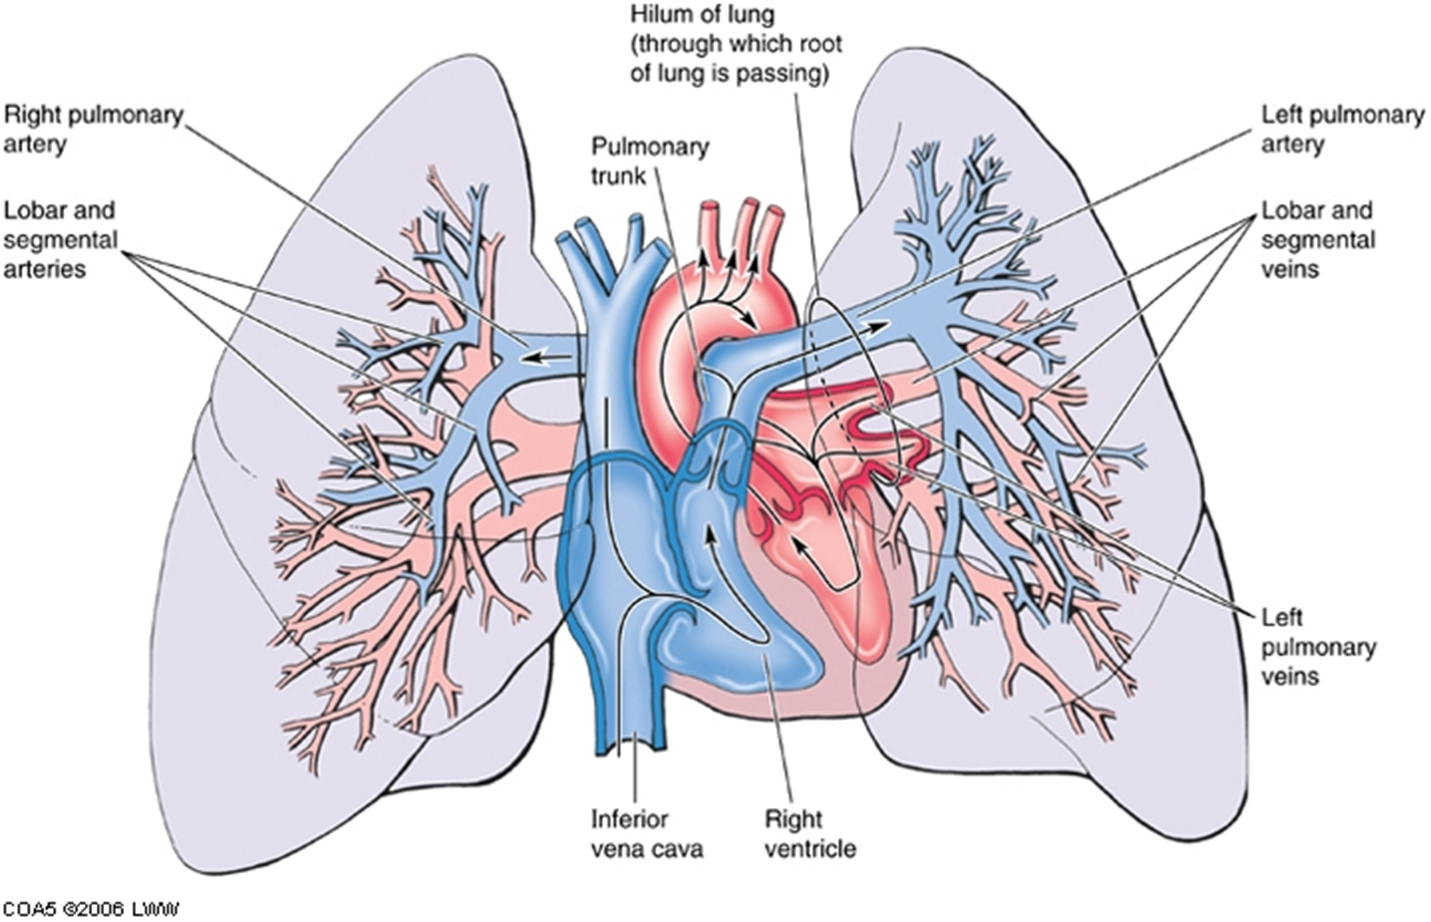

pulmonary arteries & veins

Each lung has one pulmonary artery supplying it, and two pulmonary veins draining it.

A segmental artery is usually anterior to the bronchus.

Each lung also has bronchial arteries and veins.

big picture: bronchial vs pulmonary vessels

Pulmonary arteries and veins are large - gas exchange – cardiopulmonary circulation.

Bronchial arteries and veins are small - supply & drain the tissues of the bronchial tree.